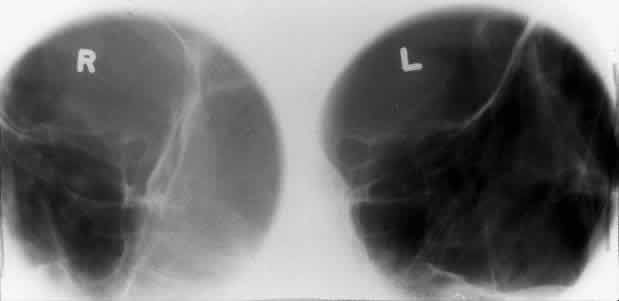

OPTIC FORAMEN (RHESE POSITION)

In 1911 Rhese14 described a projection (Fig. 6) for the evaluation of the ethmoid sinuses and the optic foramen. The patient is positioned with the orbit to be studied against the x-ray cassette. The zygoma, nose, and chin should touch the cassette. The x-ray beam is directed posterior-anteriorly at 40 degrees to the midsagittal plane.5,6 In this position the optic canal is in the inferolateral quadrant of the orbit and oriented perpendicular to the x-ray cassette.15 Variations of this standard position can be used to view other structures of interest. The Rhese projection allows assessment of the orbital apex, in particular, the optic foramen, optic strut, and the upper ethmoid sinus. A pneumatized anterior clinoid process may simulate the optic foramen. The landmark for finding the foramen is to find the planum sphenoidale; the optic foramen lies at its lateral end. The optic canal may be evaluated for expansion or compression by disease processes, such as optic nerve tumors (glioma and meningioma) and trauma. CT and magnetic resonance imaging show much better detail and therefore have replaced the use of plain films for evaluation of the optic canal.

Fig. 6. A and B. Schematic showing positioning for an oblique apical projection (Rhese position). (CR, central ray; CM, canthomeatal line) C. Radiograph of an oblique apical projection. (a, right optic canal; b, optic strut; c, superior orbital fissure; d, ethmoid sinus; e, planum sphenoidale; f, greater wing of sphenoid) (A and B; Rao VM, Gonzalez CF: Plain film radiography and polytomography of the orbit. In Gonzalez CF, Becker MH, Flanagan JC [eds]: Diagnostic Imaging in Ophthalmology, pp 1–7. New York, Springer Verlag, 1986)